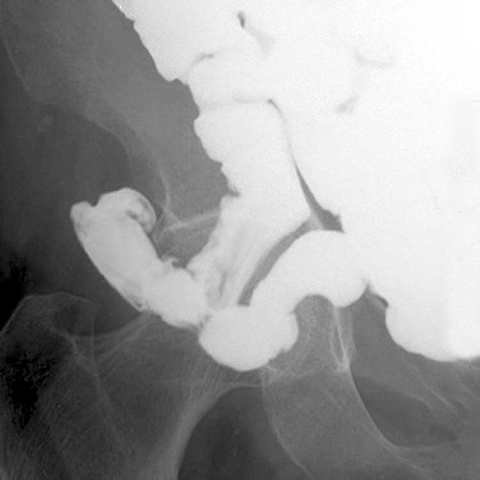

77 year-old woman presents with abdominal pain,vomiting, fever, and tachycardia [3 of 3]